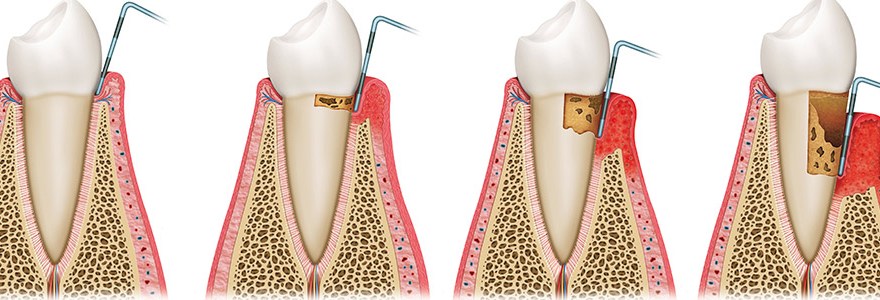

健康的牙齒跟牙齦幾乎是緊密貼合的。牙醫師會使用有刻度的牙周探針,針對每一顆牙齒進行探測檢查,沿著牙面弧度提放式行走,紀錄每一顆牙齒的牙周狀態。健康的牙周狀態,以探針探測,深度介於1-3mm之間,通常不會有滲血狀態出現,而是否有「探測時出血」,是牙齦健康的重要指標之一。當結石形成,發炎的現象越來越嚴重,患有牙周病的牙齒,探測深度會大於3mm,也就是進一步形成牙周囊袋,並且會逐漸加深。由於牙周病菌具有厭氧特性,氧氣較少的牙周囊袋正好成為孕育牙周病的溫床。牙周病菌不斷增生,散發出毒素,並且引發宿主免疫反應,造成齒槽骨吸收。當齒槽骨高度下降,便降低了對牙齒的支持力。如果置之不理、沒有妥善治療,經常導致牙齒喪失或需要拔除。